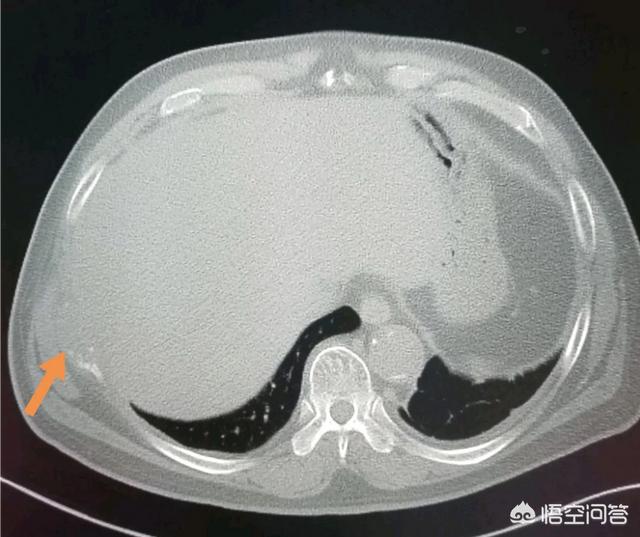

上图就是一位比较早期的食管癌病人。手术成功切除食管中下段。把食管上段和胃吻合。已经八年半了。恢复得很好。

这是一位73岁的大细胞癌。肿瘤9厘米。手术做了好几个小时。成功切除!